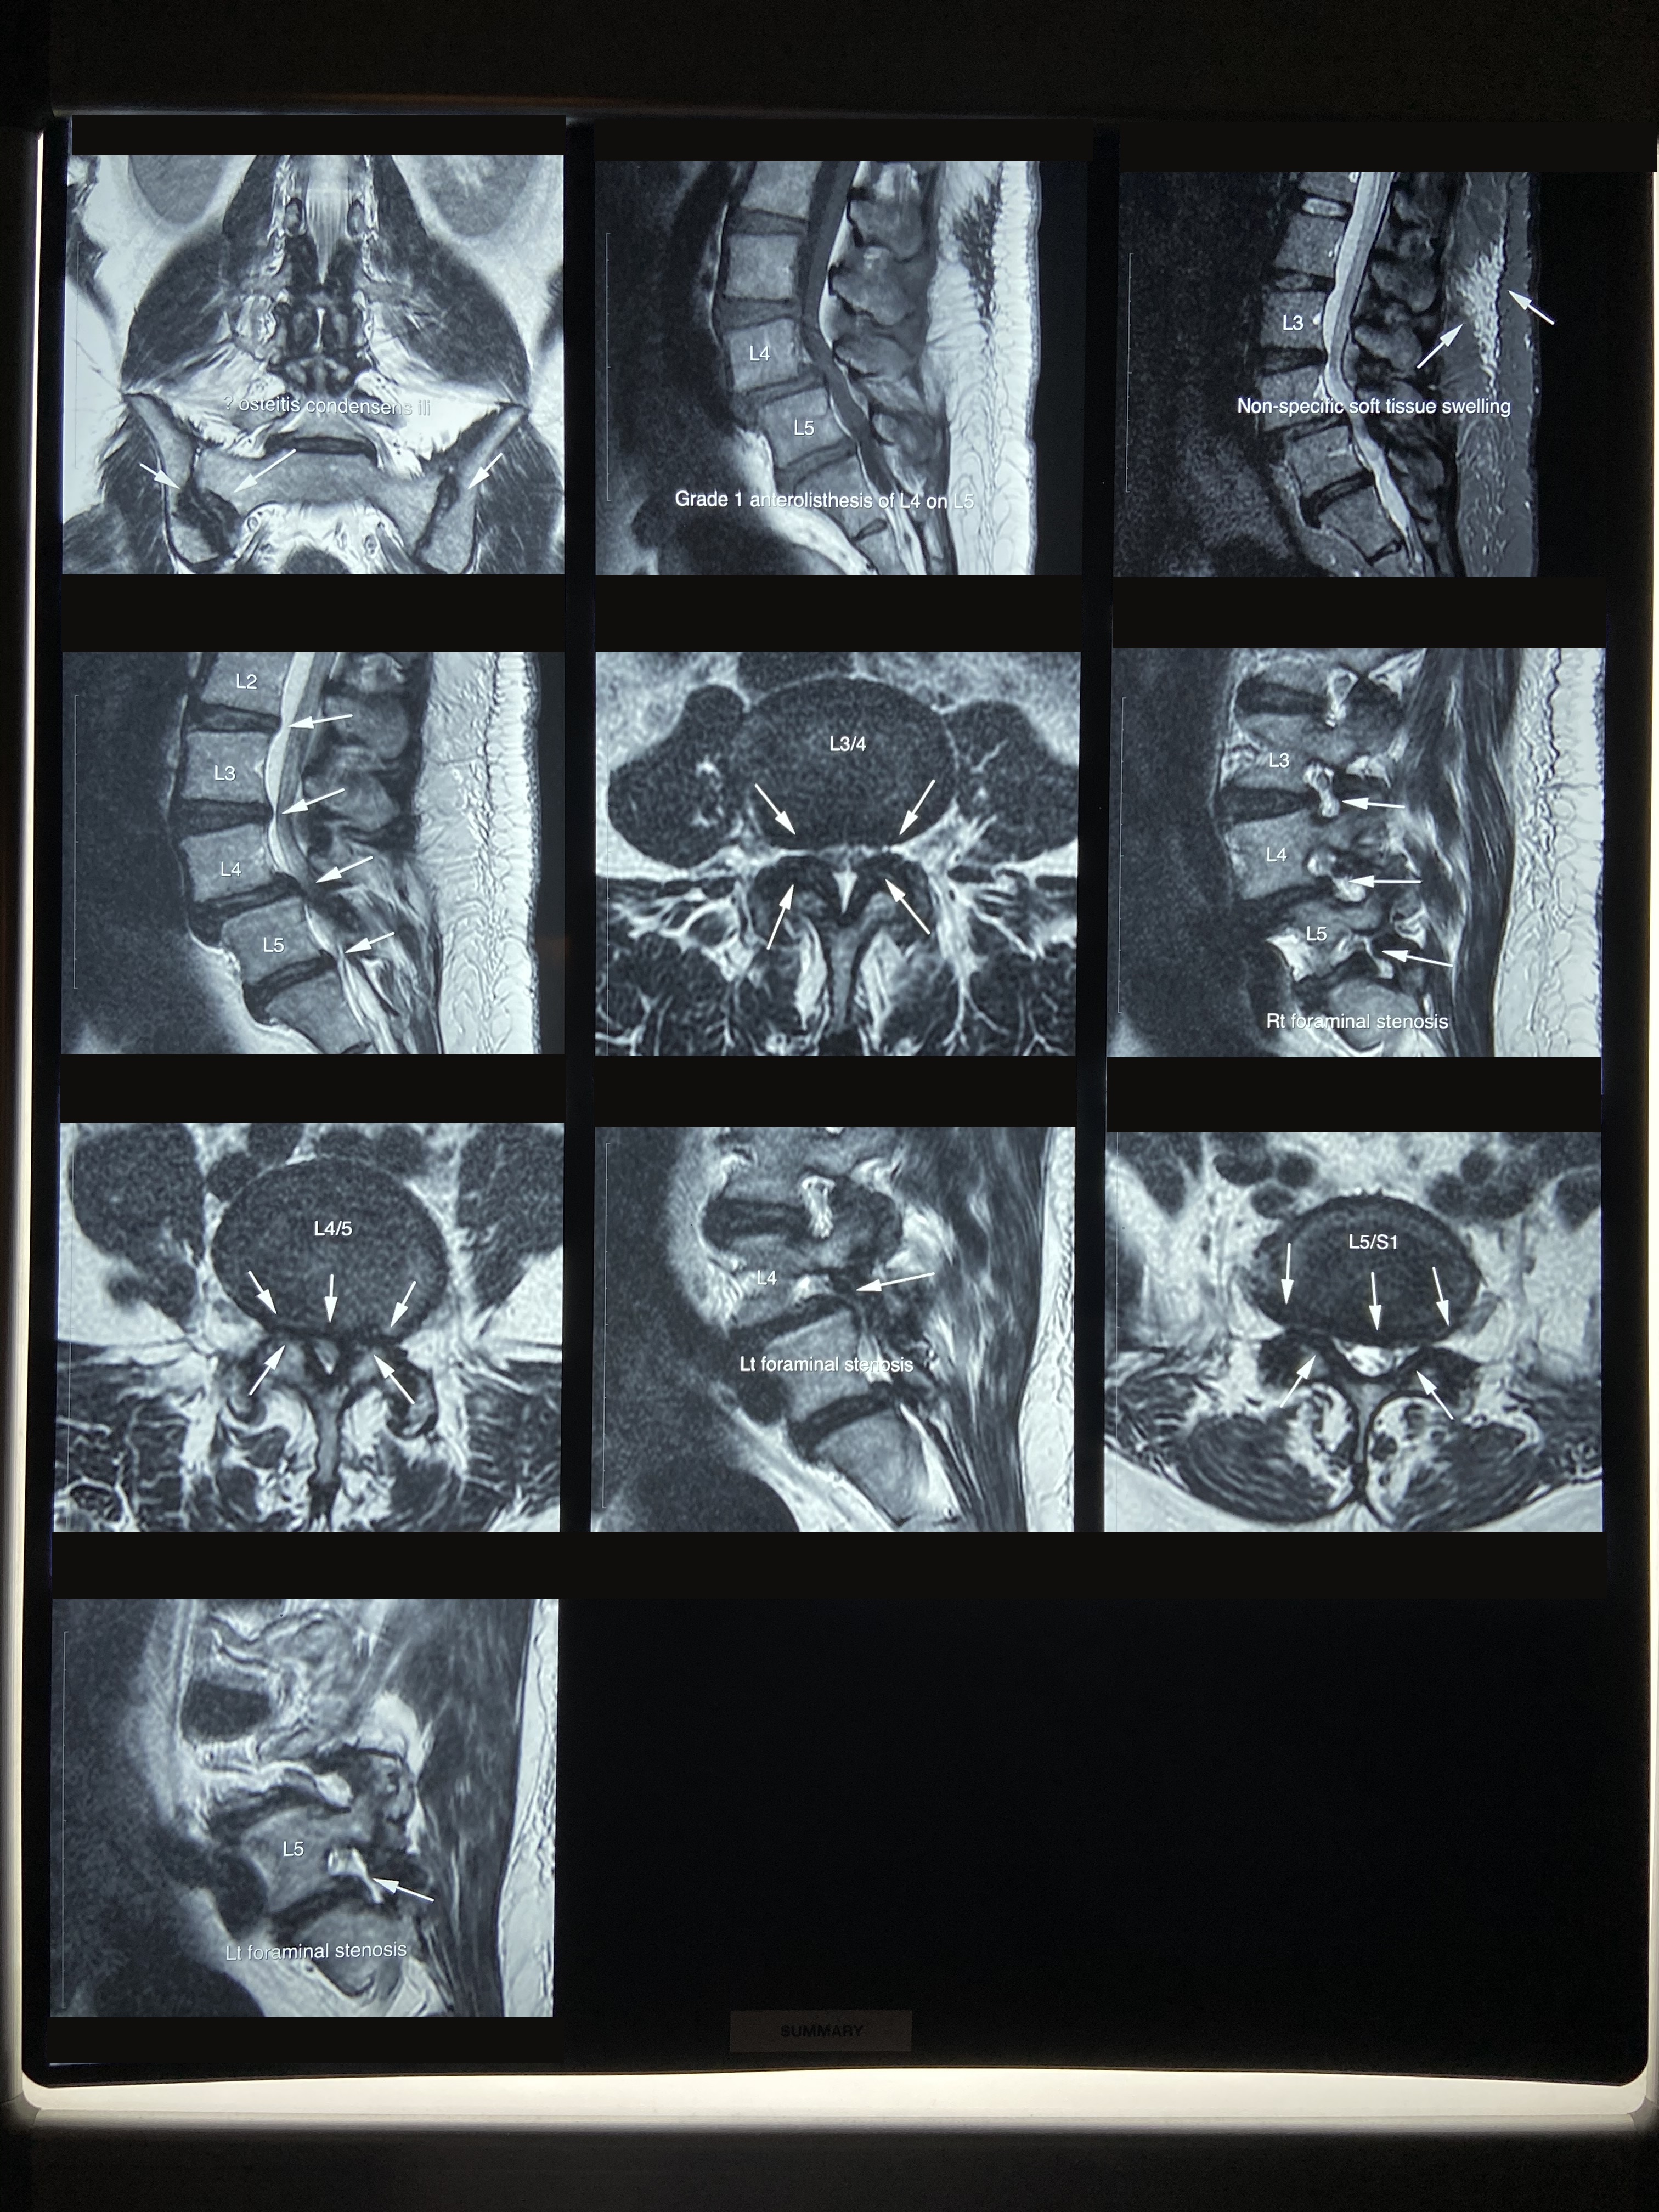

從李小姐的磁力共振報告顯示:

1)腰椎間盤突出,累及硬膜

2)椎管狹窄

3)壓迫馬尾神經

4)腰椎滑脫

5)腰椎關節退化